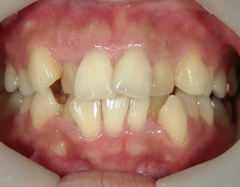

矯正歯科 治療前矯正歯科 治療前

主訴:上下の前歯の歯並びが悪いのが気になる

矯正歯科 治療前 上下左右4番 計4本を抜歯して叢生を改善しました。

no.31_1962_治療前_右.JPGno.31_1962_治療前_正面.JPGno.31_1962_治療前_左.JPG